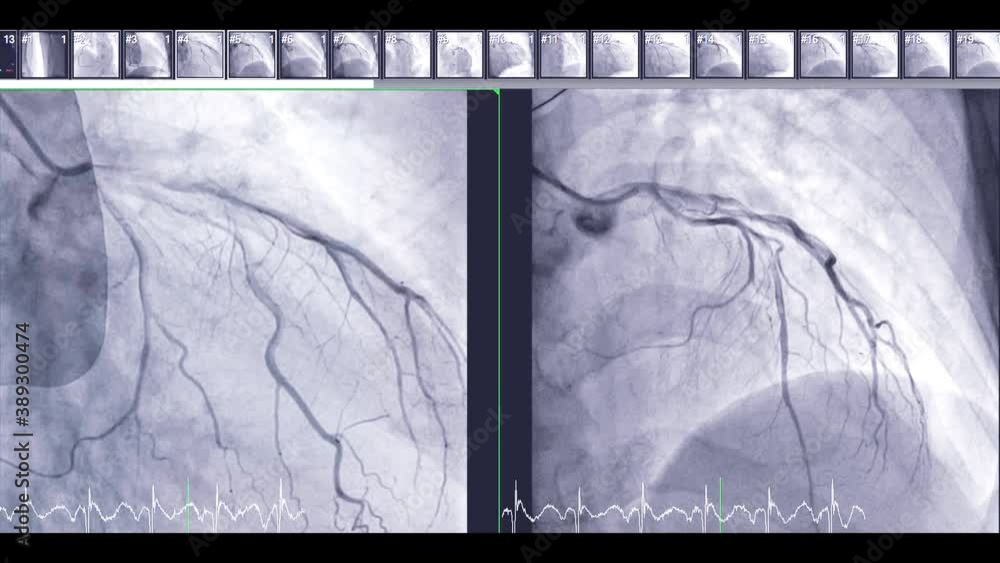

From stock.adobe.com

Coronary angiography is a test used to find out how much narrowing How Much Is A Private Angiogram Uk how much does a coronary angiogram cost? We’ll send you a questionnaire before your appointment for you to fill. Ct scan may take up to 2 hours. At goprivate.com, we have over 20 years' experience matching patients with heart. the cost of a private coronary angiogram without health insurance typically costs £2,091 at a private hospital or clinic. How Much Is A Private Angiogram Uk.